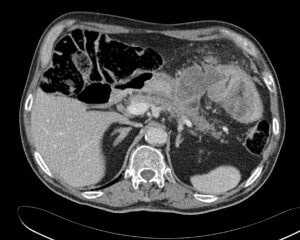

- Мультиспиральная компьютерная томография шеи, органов грудной клетки и/или брюшной полости для обнаружения зоны свища, скоплений жидкости, оценки степени поражения легочной паренхимы, плевральной полости и средостения (рисунок 3).

Вторичные бронхоэктазы и пневмофиброз нижней доли правого легкого у пациента с пищеводно-бронхиальным свищом и тотальной ожоговой стриктурой пищевода.

Желудочно-ободочный свищ в результате прорастания и распада опухоли селезёночного изгиба ободочной кишки. МСКТ